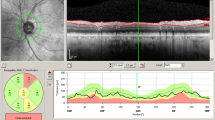

The diagnosis of AD is often based on psychometric assessments by a multidisciplinary team (neurologists, psychiatrists, and psychologist) and a neurological examination. Because of inter- and intra-individual variability, neurophysiological and neuroimaging tests have not yet been considered as criteria on which to base a diagnosis. In fact, neurophysiological as well as other paraclinical tests are recommended only on suspicion of secondary causes of dementia as part of the differential diagnosis of AD. The AD diagnosis is confirmed only with post mortem histopathology. Nonetheless, the last few decades have seen the use of structural and functional techniques as potential biomarkers that might also identify factors that may predispose individuals to AD. The optical coherence tomography (OCT) technique for the measurement of the peripapillary RNFL, the macular thickness and volume, has been demonstrated as useful for the demonstration of significant retinal changes in patients that roughly correlate with the severity of the disease (Fig. 13.2).